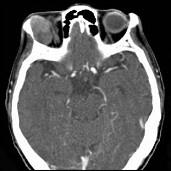

问题 男性,41岁,右侧眶外上方肿胀,可触及无痛性包块,CT及MRI检查如图所示,请选择最可能诊断()

选项 A.眶内血管瘤 B.眶内结核 C.眶内炎性假瘤 D.泪腺混合瘤 E.眶内囊肿

答案 D